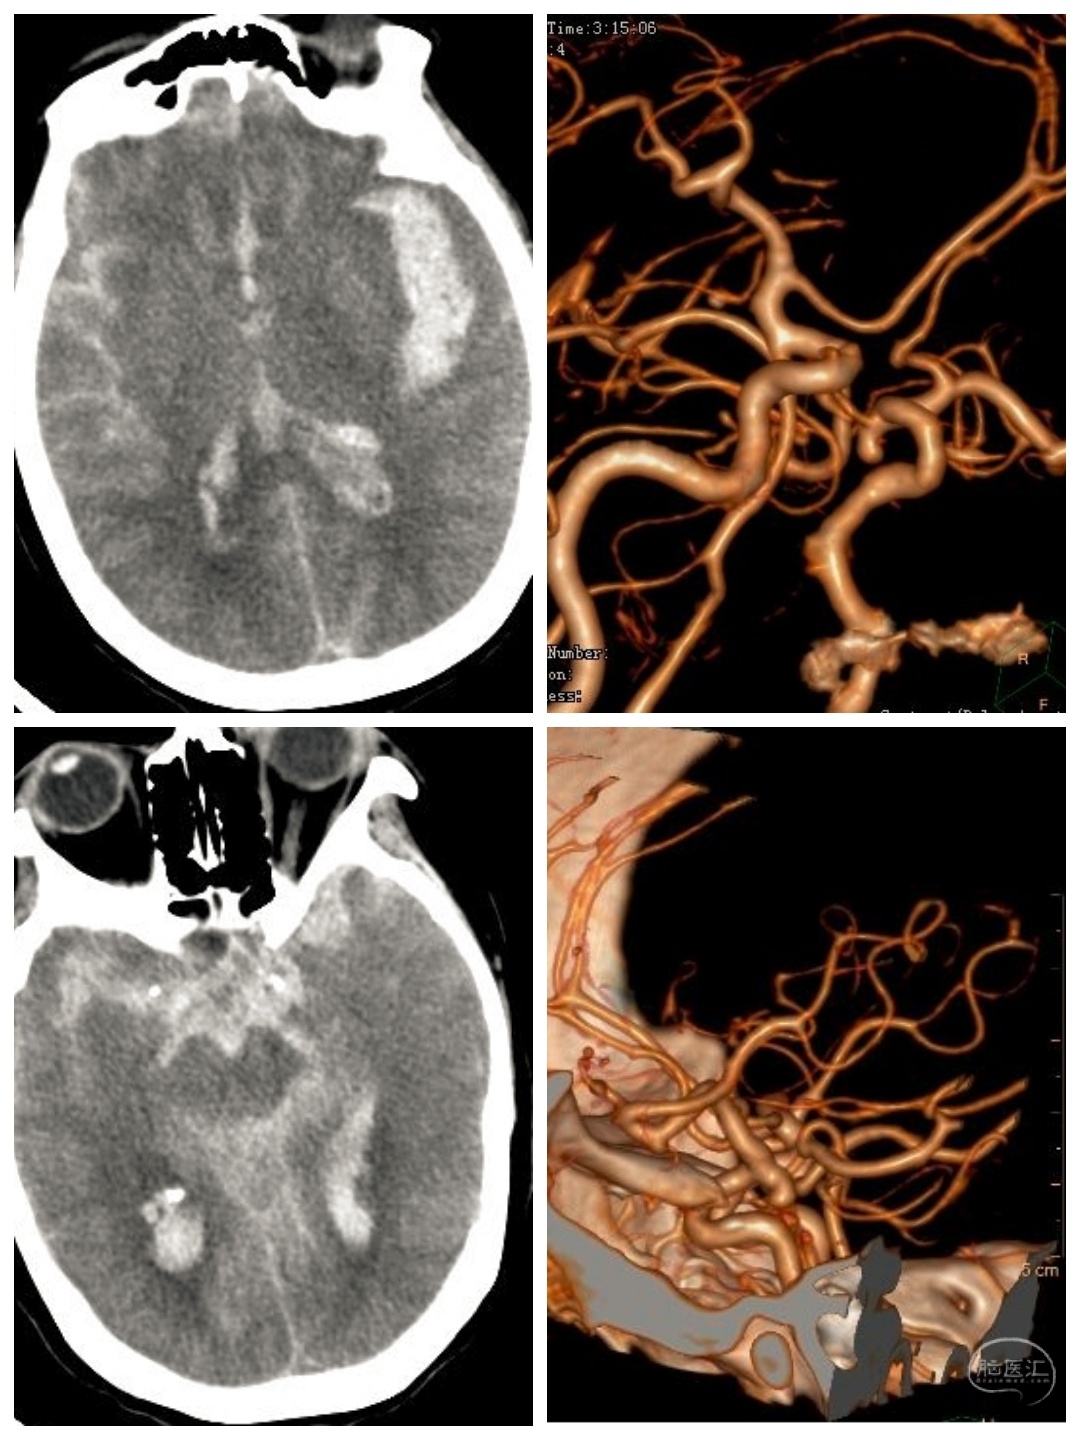

袁某某,女性,65岁,“突发意识障碍3小时”急诊入院。查体:神志中昏迷,双侧瞳孔4 mm,对光反射消失,Hunt-Hess IV级,左侧肢体刺痛屈曲,右侧肢体刺痛异常屈曲,病理征阳性。

CT检查提示左侧外侧裂,鞍上池以及脑室出血;CTA提示左侧后交通动脉瘤破裂出血。如此高等级的动脉瘤破裂出血,预后极差,九死一生!

急诊行左侧后交通动脉瘤夹闭+血肿清除+双侧脑室穿刺引流术。术后予以扩容,改善微循环,控制血压等综合治疗。尽一切可能,最快的清除脑内血肿!